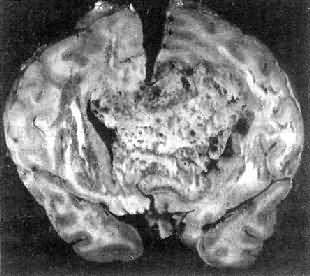

图16-26 髓母细胞瘤 瘤细胞较小,着色深,密集排列,有菊形团形成 髓母细胞瘤恶性程度高,预后差。 (三)脑膜瘤 脑膜瘤(meningioma)可来源于脑膜的各组成成分如蛛网膜细胞,纤维母细胞或血管,其中多数来源于蛛网膜颗粒中的蛛网膜细胞。本瘤大多生长缓慢,良性类型可完全无症状,在70岁以上老人的尸检中,发现无症状的脑膜瘤不在少数,无症状脑膜瘤占颅内肿瘤的14%。脑膜瘤患者多为40~50岁中年人,女性较男性多。 肿瘤的好发部位与蛛网膜颗粒所在部位相同,常见于上矢状窦旁大脑镰两侧,蝶骨嵴,嗅沟,小脑脑桥角;在脊髓则以胸段为多见,一般颅内脑膜瘤较脊髓脑膜瘤多2倍。 肉眼观,肿瘤呈球形,分叶状或不规则形,质实或硬,边界清楚,周围脑组织受压成凹陷切迹(图16-27)。少数肿瘤呈斑块状覆盖较广泛区域,甚至整个脑半球,称为斑块型脑膜瘤。肿瘤质地硬,切面灰白色,呈颗粒状、条索旋涡状,有的质地似砂砾样,乃由于有多量砂粒体存在。

图16-27 脑膜瘤 于大脑两半球间有一近似球形肿瘤,边界清楚,周围脑组织受压萎缩 由于脑膜瘤的组织来源复杂,其组织学图像也可呈现下列基本类型: (1)脑膜细胞型(融合细胞型):瘤细胞胞浆丰富,边界不清楚,胞核椭圆形,细胞排列呈分叶状或旋涡状,为纤维间质条索所分隔。 (2)纤维细胞型:瘤细胞呈长梭形,排列成致密的交织束状结构,其间有网状纤维及胶原纤维,有时胞核呈栅状排列。 (3)过度(混合)型:脑膜细胞与纤维细胞混合,排列成分叶状,中央为脑膜细胞,周围为纤维细胞,常形成旋涡状结构(图16-28),其中常包含有同心层状结构的砂粒体,乃变性肿瘤细胞及钙盐沉积。肿瘤质地硬,似砂砾状。